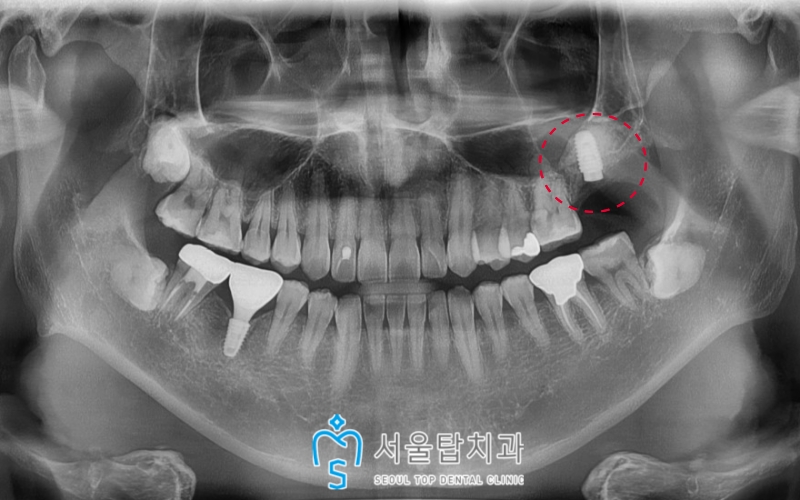

파노라마 사진을 촬영하여 확인해 보았더니

사랑니가 바로 앞

왼쪽 위 두 번째 큰 어금니(#27)의

치근(치아뿌리)을 일부 침범하게 되면서

치근 우식이 관찰되었습니다.